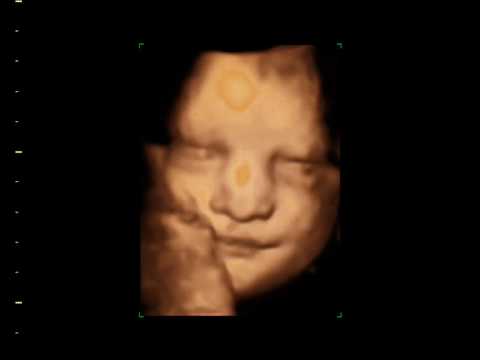

Normal and Abnormal Fetal Face Israel Goldstein and Zeev Wiener Rambam Health Care Campus, Haifa Indications for ultrasound examinat ion of the fetal face (Pilu et al., Fig. 3. 3D pictures of the fetal face. Mimics of face: a. kiss, b: open mouth an d tongue, c: ... Read Full Source

Diagnostic Evaluation Of The Fetal Face Using 3-Dimensional ...

Diagnostic Evaluation of the Fetal Face Using eyes, nose, lips, and chin in a single frontal rendered image tal face with 3D ultrasound (3DUS) as well as 2-dimensional (2D) ultrasound. Rendered images allow the face to be dis- ... Fetch Full Source

Penny Wicher, RDMS, the owner of LITTLE LIFE IMAGING 3D/4D ULTRASOUND and even open and close their eyes during the 3D/4D live motion ultrasound. Little Life Imaging now offers evening hours to accommodate working families. They are open until 8pm, Monday through Friday, to help give everyone ... Retrieve Content

3D Ultrasound - YouTube

3D ultrasound of Aidan on 19 August 2006. Category People & Blogs; License Standard YouTube License; Show more Show less. Junior with his eyes open - Duration: 0:35. dizonewart 39,895 views. 0:35 Caesarea National Park ... View Video